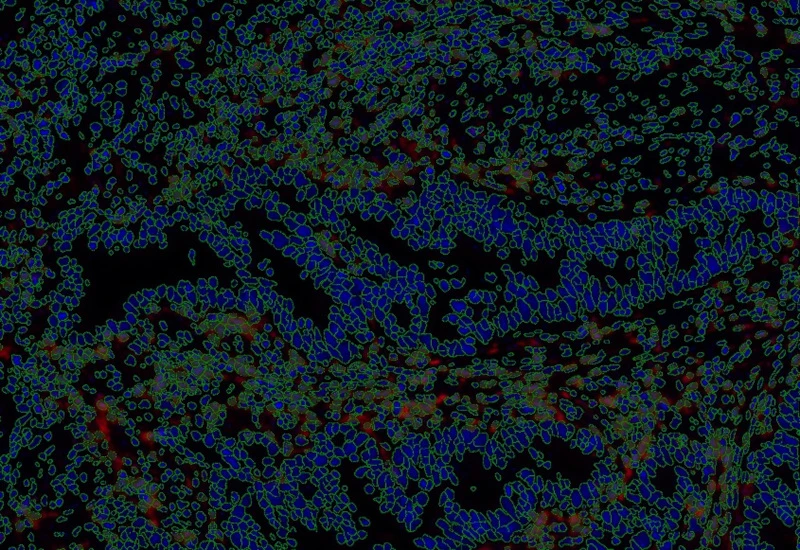

IF Immune status in situ

Characterize immune cell phenotypes relative to detected metastructures (e.g. tumors, glands), define distance ranges, measure cell-to-boundary distances inside/outside, and export up to 20 intensity, statistic, and morphometric parameters per cell compartment.

The IF Immune Status in Situ App provides phenotypic characterization of immune cells in reference to detected metastructures (e.g. tumors, glands) and measures the distance of detected cellular objects to the metastructure boundary (within and/or outside). Distance ranges can be defined. Each segmented cell compartment is measured for up to 20 intensity, statistic and morphometric parameters, as is the distance of each cell to the areas boundary.

Nuclei detection

Tumor detection

Proximity measurements: 25-50µm